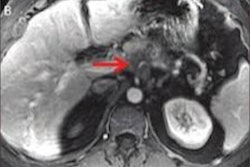

The company started a program that allowed participants to undergo PET/CT, noncontrast brain and pelvis MRI, and abdominal ultrasound exams every two years over a 10-year timespan. Employees could also undergo annual screenings such as chest x-ray, upper gastrointestinal x-ray with oral contrast, fecal occult blood test, prostate-specific antigen testing (for men over 55), and mammography (for women over 40). The program cost $1,350 per employee every two years; this cost was split between the company and participants.

For the imaging exams, employees were categorized into full participation (five screenings), partial (more than once and less than five), and no participation groups. Anzai's team measured the cancer detection rate, rate of cancer-related death, and cancer-related costs of care. Of 1,213 employees, 543 were full participants, 318 were partial, and 352 did not participate in the imaging protocol. Across all three groups, 54 cancers were identified, with the majority in the full and partial participation groups being early stage (0 to 1).